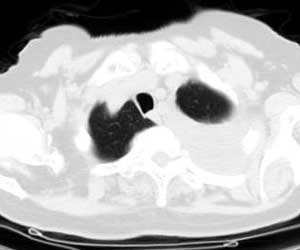

标题: CT0563:病历讨论,胸膜间皮瘤?

测ct值3-6hu,

既然ct值是3-6hu,还不如考虑包裹性积液。

请上传纵隔窗。目前还是支技包裹性积液(明显梭形),即使是间皮瘤并积液也少梭形的。

从图片看,包裹性积液好象更合理,梭形,ct值3-5hu(在哪看到的?);胸膜间皮瘤如此规则,不多见。

左侧背部胸膜肥厚,伴包裹性积液,不考虑间皮瘤.

同意以上各位的高见,首先考虑包裹性积液,1.胸膜间皮瘤积液量一般较大,以游离性积液更为常见,2.可以看到增厚的胸膜结节